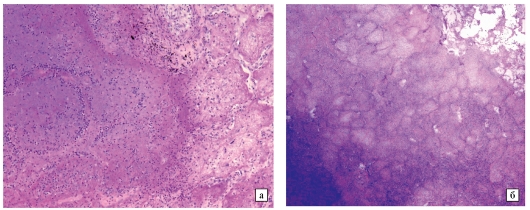

Микроскопический взгляд на мишитарный туберкулез легкого: фотодокументация

Раздел: Снимки-откровения